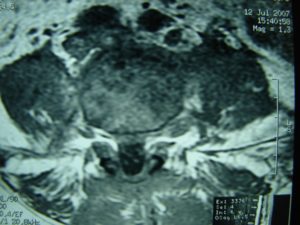

Μαγνητική Τομογραφία της Ο.Μ.Σ.Σ. (13/06/2007) Ακολουθία Τ1 και Τ2

Οβελιαία τομή (α,β) Παρατηρείται η ύπαρξη Επισκληριδίου Αποστήματος στο επίπεδο Ο3-Ο4 που προκαλεί μεγάλη στένωση του σπονδυλικού σωλήνα, με απώθηση του νωτιαίου σάκου. Διαπιστώνεται επίσης η ύπαρξη παρα-σπονδυλικού αποστήματος

Εγκαρσία τομή (γ,δ) Παρατηρείται η ύπαρξη Επισκληριδίου όπως επίσης και προ-παρασπονδυλικού αποστήματος.